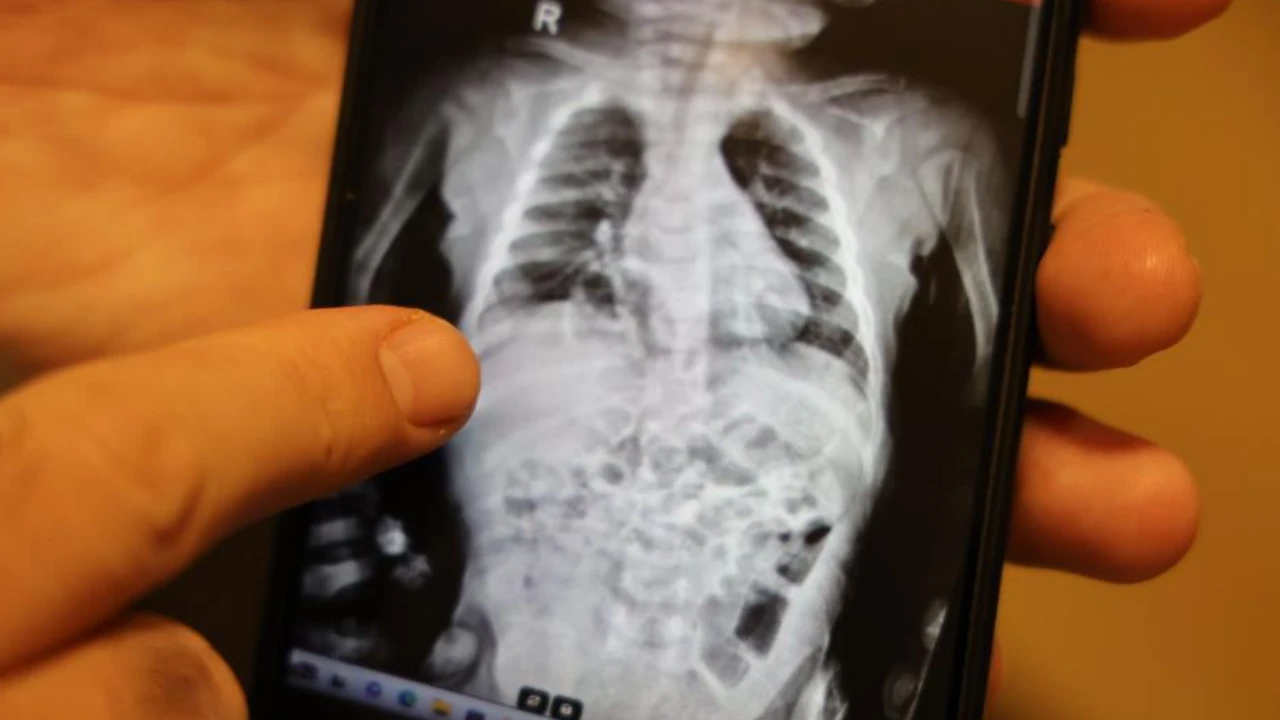

Operasyonu gerçekleştiren Çocuk Cerrahı Op. Dr. Taner Kamacı, hastalığın “Morgagni hernisi” olarak adlandırılan çok nadir bir diyafram fıtığı türü olduğunu belirterek, “Yaklaşık 200 bin doğumda bir görünen nadir vaka. Türkiye’de geçen yıl doğan bebek sayısına göre yılda yalnızca beş bebekte bu rahatsızlık görülüyor. Akciğer filmleri ve tomografiyle tanıyı kesinleştirdik” dedi.